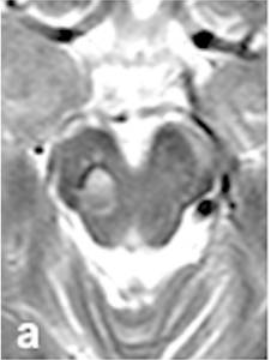

2. 第二次警报(术前6个月): 复查的磁共振成像(MRI)再次拉响警报——提示病灶区域有轻微的新发出血迹象!令人惊讶的是,患者依然没有任何不适症状。

术前6个月

术前MRI清晰显示一个22mm的出血性病灶向尾侧延伸(图b-c)